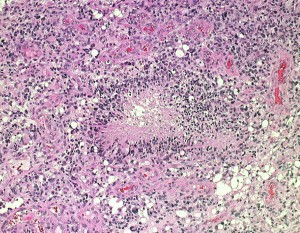

一部で,細胞密度が高く,核の腫大とクロマチンの増量,核間距離の短縮があり,核分裂像が認められ,MIB-1染色率が10%です。組織学的には退形成性乏突起膠腫グレード3とされました。

IDH変異あり,1P/19q欠失あり,ATRX変異なしです。

同じ患者さんからの2カ所の病理標本です。左は乏突起膠腫グレード2と診断できますし,右は退形成性星細胞腫グレード3と診断できます。光顕診断では,両方合わせて,退形成性乏突起星細胞腫グレード3となります。ちなみに,olig2 強陽性,MIB-1 9%,1p/19q codeletionがありました。遺伝子診断を加えると退形成性乏突起膠腫となります。乏突起膠細胞系腫瘍では,術中迅速病理診断や定位脳生検術での診断は誤診を招くことが多くて危険です。

部分像だけでは星細胞系腫瘍と見分けはつかない

この部分のみを一見するとanaplastic astrocytomaです。しかし,他の大部分がoligoastrocytomaであり,かつての組織診断ではanaplastic oligoastrocytoma AOA WHO grade IIIです。

左側の病理像はanaplastic oligodendroglioma AO あるいはoligodendroglioma ODです。しかし,右の画像の様にpseudopallisading (necrosis)を示す部分があり,WHO grade 4と診断したくなるのですが,oligodendrglioma grade 3 ではnecrosisが混在してもgrade 3としてよいのです。